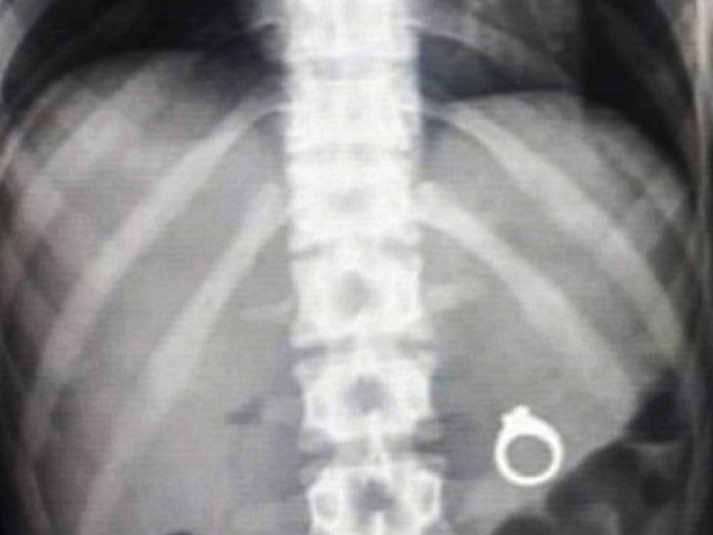

Вот буквально несколько примеров тех вещей, которые были обнаружены в человеческом желудке.